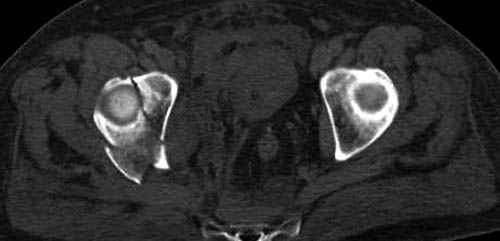

Наш недавний случай перкутанной фиксации "методом

Сиэтла" спицами 2.8 мм с резьбой на конце.